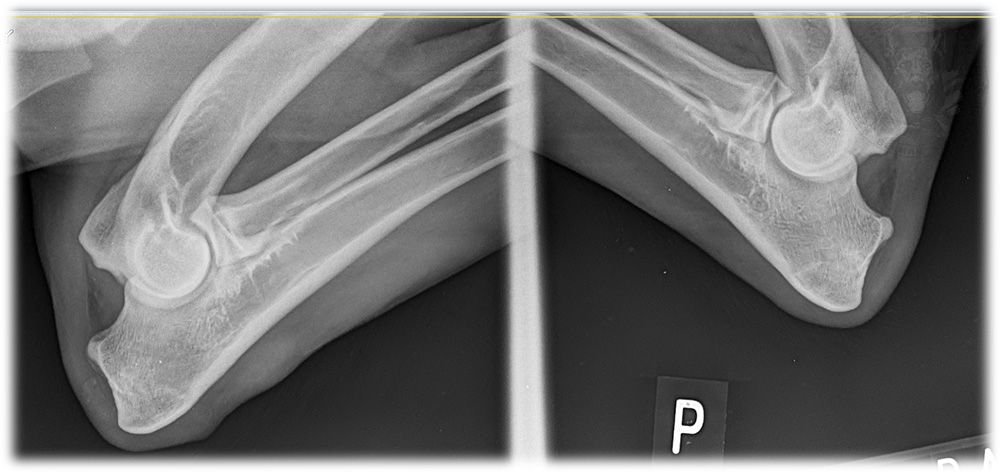

性别:公 生日:2016-11-6 FCI国际血统证编号: Titled: Show: Breed Survey: Elbows,hips: 其它: |  侧面   蹲坐   俯卧   俯卧2   血统1   血统2   肘关节   髋关节   腰侧 |

性别:公 生日:2015-9-17 Titled:ZVV1, BH Show:vyborny (excellent) Breed Survey:1st class 5JY1/P Elbows,hips:0/0 其它:身高66CM |  达布尔-站姿   达布尔-蹲坐1   达布尔-蹲坐2   达布尔-俯卧1   达布尔-俯卧2   达布尔-血统证 |

性别:母 生日:2011-9-29 FCI国际血统证编号:CMKU/DS/83758/11 Titled:ZVV1 Show:vyborny (excellent) Breed Survey:1st class 5JY1/p Elbows,hips:0/0 DNA已登记注册 其它:待售种母 |  AttaAdnaf站姿  AttaAdnaf蹲坐  AttaAdnaf俯卧1  AttaAdnaf俯卧2  AttaAdnaf血统证1  AttaAdnaf血统证2 |

性别:公 生日:2016-2-18 FCI国际血统证编号: Titled: Show: Breed Survey: Elbows,hips: 其它: